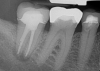

Fig 3. Preoperative maxillary left bicuspid.

Figure 3

The patient presented with temperature sensitivity and pain during mastication (Figure 3). Local anesthesia was delivered, and steps 1 through 4 were performed.